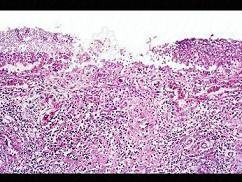

- 多项选择题根据图,有关菌痢的病理改变正确的是 ( )

A、粘膜下层、肌层、浆膜层有明显的炎症反应

B、大约一周左右,假膜开始脱落,形成大小不等,形状不一的“地图状”溃疡如图

C、整个肠粘膜有假膜覆盖,粘膜上皮及腺体大片消失

D、假膜主要为纤维素、坏死的肠粘膜、细菌、嗜中性粒细胞及红细胞等,部分有脱落

E、黏膜充血、水肿、中性粒细胞和巨噬细胞浸润